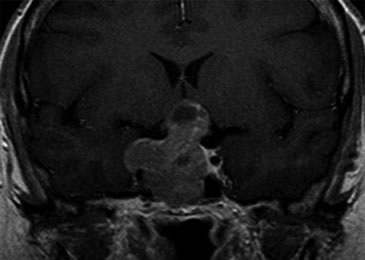

Se realizó una campimetría que evidenció una hemianopsia heterónima temporal. Una RM (Resonancia Magnética) posterior confirmó el hallazgo de adenoma hipofisario de 42 x 34 x 25 mm que realzaba moderadamente con en el contraste paramagnético, con varios quistes de retención glandular (el mayor de aproximadamente 1 cm de diámetro), con extensión supraselar e invasión del seno esfenoidal y seno cavernoso derecho con desplazamiento y compresión del quiasma óptico y del tallo hipofisario (Figuras 1 y 2).

Figura 2. Corte coronal en secuencia T1 con gadolinio.